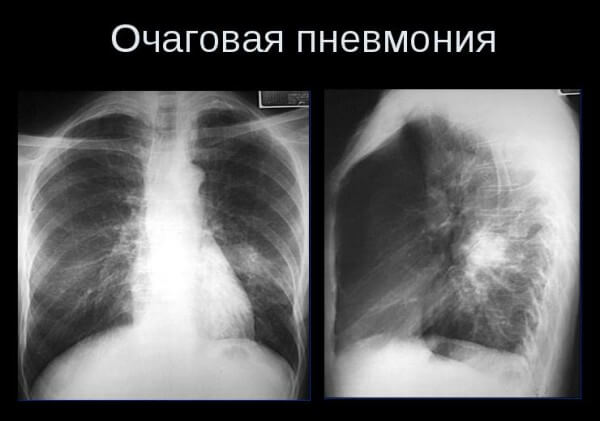

Исследование рентгеном легких: Обычно очаговые или сегментарные затемнения легочной ткани наблюдаются в нижних частях легких с нечеткими и размытыми внешними границами.

- Исследование грудной клетки методом рентгенографии в двух проекциях

Для определения точного диагноза необходимо провести рентгеноскопию легких и два клинических анализа.

Необходимо подчеркнуть, что изменения на рентгенограмме становятся заметными ближе к концу второй или третьей недели, а иногда и позже. Симптомы очаговой пневмонии, вызванной стрептококками, могут привести к образованию абсцесса и эмпиемы плевры.

Для обеспечения точности результатов анализов необходимо выполнить рентгенографию грудной клетки или компьютерную томографию.

При проведении рентгеновского обследования можно обнаружить участки затемнения. Если на рентгеновском снимке затронуты несколько сегментов и видно, как они объединяются в один более крупный, это указывает на наличие очагово-сливной пневмонии. Симптомы этого вида пневмонии более сложны и выражены более ярко, проявляются в форме дыхательной недостаточности и признаков отравления. По клиническим проявлениям очагово-сливная пневмония напоминает крупозное воспаление лёгких и всегда требует госпитализации в стационаре.

Изучение рентгеновскими снимками грудной клетки и проведение компьютерной томографии являются важными исследованиями с множеством информации. Обычно выявляют очаговые темные участки на заднем плане инфильтрации как в области бронхов, так и вокруг сосудов.